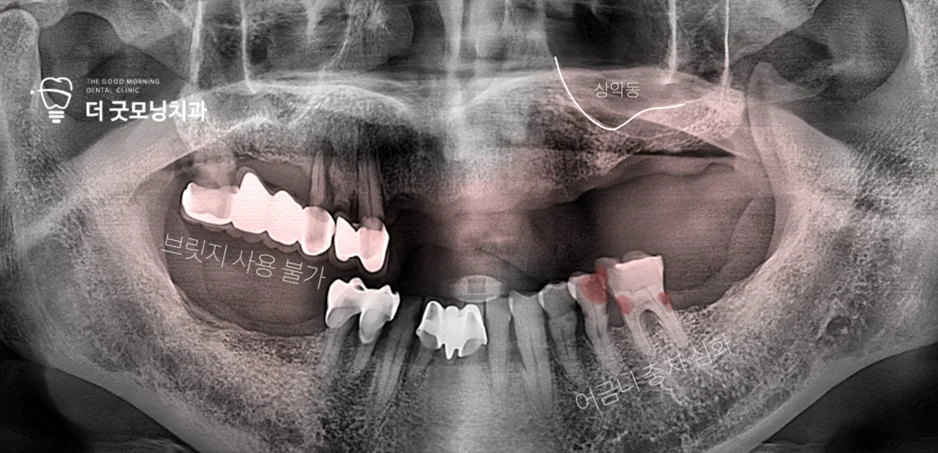

Step 1. 초진 상태 확인

초진 시 여러 치아가 이미 상실된 상태였으며, 하악에 남아있던 어금니 2개는 심한 충치로 보존이 불가능한 상태였습니다. 우측 상악에는 브릿지가 씌워져 있었으나 지대치의 이차 우식 및 파절이 진행되어 잔존치 발치가 필요한 상황이었습니다.